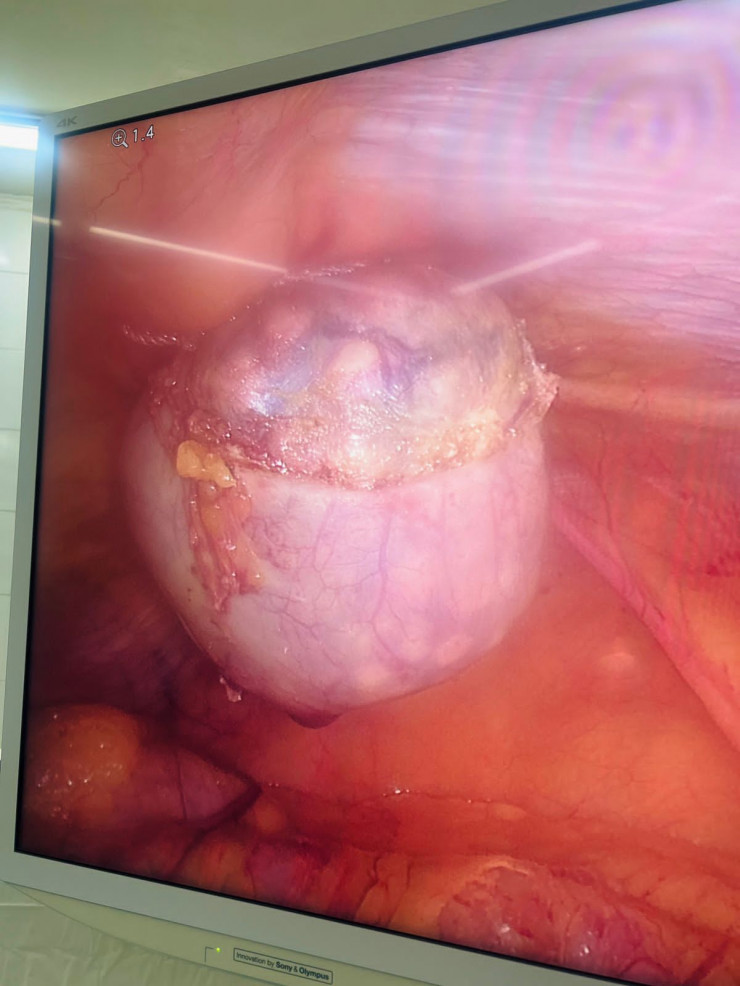

Более 1730 камней извлекли алматинские хирурги из желчного пузыря пациентки, передает корреспондент Tengrinews.kz.

62-летняя женщина поступила в городскую клиническую больницу №7 города Алматы в экстренном порядке с жалобами на боли в правом подреберье, тошноту, рвоту, сухость во рту. После обследования больной был выставлен диагноз: "Желчекаменная болезнь. Острый калькулезный холецистит". На следующий день ей была проведена лапароскопическая операция.

После удаления желчного пузыря из него было извлечено 1735 конкрементов диаметром от нескольких миллиметров до 1,5 сантиметра.

Специалисты отмечают, что желтый цвет камней обусловлен повышенным содержанием холестерина. Фото предоставлено пресс-службой ГКБ №7 города Алматы

"Эта операция обновила мой рекорд: в этот раз обнаружено более 1730 конкрементов (камней), и это только в желчном пузыре. В целях сохранения здоровья и предупреждения осложнений, связанных с ЖКБ, настоятельно рекомендую проходить профилактические и скрининговые осмотры", - отметил заведующий отделением хирургии №2 ГКБ №7 профессор Муса Сахипов.

Оперативное вмешательство прошло успешно, на 4-й день после операции больная выписана на дальнейшее амбулаторное наблюдение.